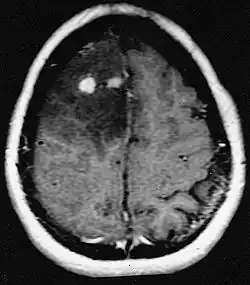

Primäre ZNS-Lymphome

Primäre Lymphome des Zentralnervensystems machen etwa 2 Prozent bis 3 Prozent aller Hirntumoren von Patienten mit einem normalen Immunsystem aus. Sie treten häufiger bei Männern im Alter von 55 bis 60 Jahren auf. Fast die Hälfte aller Lymphome tritt bei Patienten über 60 Jahren und etwa ein Viertel bei Patienten über 70 Jahren auf. Die Inzidenz scheint mit dem Alter zuzunehmen, der Grund jedoch ist noch ungeklärt. Einem höheren Risiko für ein ZNS-Lymphom ausgesetzt sind Patienten mit einem geschwächten Immunsystem, damit diejenigen, die sich einer Organtransplantation unterzogen haben, einen angeborenen Immundefekt oder eine Autoimmunerkrankung haben oder mit dem Humanen Immundefizienz-Virus infiziert sind. Mit dem HI-Virus assoziierte Hirnlymphome sind mit dem Epstein-Barr-Virus verbunden, insbesondere bei Patienten mit CD4-Lymphozytenanzahl unter 500 Zellen pro Kubikmillimeter im Blut.[40] Die meisten ZNS-Lymphome sind vom Typ her diffuse großzellige B-Zell-Lymphome.

Die Patienten leiden an einer Vielzahl charakteristischer Symptome einer fokalen oder multifokalen massiven Läsion. Das Kernspintomogramm zeigt normalerweise Tumoren mit homogener Kontrastverstärkung innerhalb der tiefen periventrikulären weißen Substanz. Multifokalität und inhomogene Verstärkung sind typisch für Patienten mit geschwächtem Immunsystem. Extrem wichtig ist die Analyse des ZNS-Lymphoms bei der Differentialdiagnose von Hirnneoplasien. Es sollte beachtet werden, dass die Verabreichung von Kortikosteroiden zum vollständigen Verschwinden der Verstärkung führen kann, was Diagnose der Läsionen erschwert. Wenn das ZNS-Lymphom in der Differentialdiagnose berücksichtigt werden soll, sollten folglich Kortikosteroide vermieden werden, es sei denn, der Masseneffekt verursacht ein ernstes und unmittelbares Problem beim Patienten.